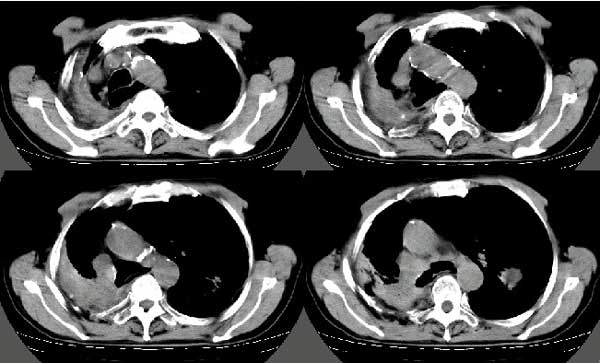

以下是引用扬仪在2005-5-12 20:46:40的发言:[br]右肺呈术后改变;双侧肺野散在分布斑片状、点状高密度病灶,(似可见“树芽征”);左上尖后段见斑团状高密度病灶(2个层面?),边缘毛糙,段性分布,与斜裂相邻,临近胸膜粘连;增强示病灶边缘强化,内呈水样密度;心影、纵隔右移,内可见4r淋巴结肿大。[br]意见:1、双肺继发性肺结核,左上为干酪病灶;[br] 2、矽肺合并感染;[br] 3、建议抗痨+抗炎。 [br]愚人之见,请高人指教!